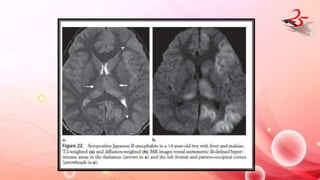

FLAVI VIRUS ENCEPHALITIS

• Eg : Japanese encephalitis, West nile fever , Murray valley fever

IMAGING FINDINGS:

• Symmetric involvement of deep grey matter

JE : T2 hyperintensity in B/L posteromedial thalamus

• Intralesional hemorrhages + DWI R

• Less common sites : basal ganglia, substantia nigra, red nucleus, pons, hippocampi,

cerebral cortex, and cerebellum.

• JE and Murray valley fever involve THALAMUS

• West nile fever : B/L involvement of thalamus , caudate and lentiform

nucleus

FLAVI VIRUS ENCEPHALITIS •Eg : Japanese encephalitis, West nile fever , Murray valley fever IMAGING FINDINGS: • Symmetric involvement of deep grey matter JE : T2 hyperintensity in B/L posteromedial thalamus • Intralesional hemorrhages + DWI R • Less common sites : basal ganglia, substantia nigra, red nucleus, pons, hippocampi, cerebral cortex, and cerebellum. • JE and Murray valley fever involve THALAMUS • West nile fever : B/L involvement of thalamus , caudate and lentiform nucleus